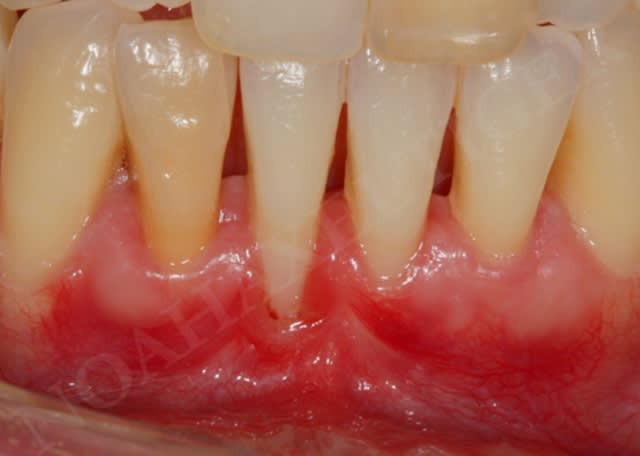

14/03/2009 à 20h54

Je vous poste les dernières photos cliniques du cas en question qui est en cours de maturation tissulaire. (je vous met la photo initiale aussi)

Le patient est content du résultat ... moi aussi ;-))